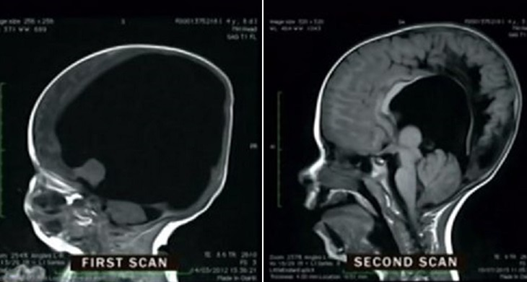

Хүүгийн тархи маш их шахагдсан аж. Тэрээр юм харж, юм сонсож, ярьж чадахгүй, түүнчлэн өөрөө хоолоо идэж чадахгүй байж мэднэ гэж эмч нар үзэж байсан ч, эцэг, эх нь эмчилгээ хийлгэж, анхаарал тавьснаар одоо Ной бараг эрүүл саруул болжээ.

Эцэг, эх нь Австралийн нэг клиникт хандаж, энэ эмнэлгийн мэргэжилтнүүд танин мэдэх чадварыг сайжируулдаг дасгал, физик эмчилгээг хослуулах аргаар өвчтөнүүдийнхээ тархийг дасгалжуулдаг байна.

Одоо эмч нар Ной Уоллын бүрэн хэвийн аж төрөх магадлалыг нааштай үнэлж, харин телевизийн хөтлөгчид хүүг жинхэнэ гайхамшигийн жишээ хэмээн нэрлэж байна.